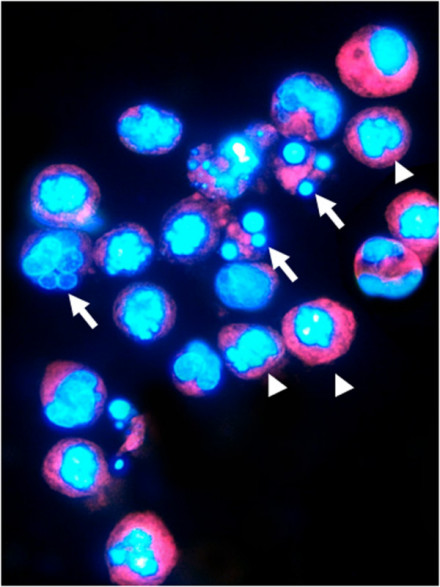

2.荧光显微镜和共聚焦激光扫描显微镜

一般以细胞核染色质的形态学改变为指标来评判细胞凋亡的进展情况。

常用的DNA特异性染料有:HO 33342 (Hoechst 33342),HO 33258 (Hoechst 33258),DAPI。三种染料与 DNA的结合是非嵌入式的,主要结合在DNA的A-T碱基区。紫外光激发时发射明亮的蓝色荧光。

Hoechst是与DNA特异结合的活性染料,储存液用蒸馏水配成1mg/ml的浓度,使用时用PBS稀释成终浓度为2~5mg/ml。

DAPI为半通透性,用于常规固定细胞的染色。储存液用蒸馏水配成1mg/ml的浓度,使用终浓度一般为0.5 ~1mg/ml。

结果评判:细胞凋亡过程中细胞核染色质的形态学改变分为三期:Ⅰ期的细胞核呈波纹状(rippled)或呈折缝样(creased),部分染色质出现浓缩状态;Ⅱa期细胞核的染色质高度凝聚、边缘化;Ⅱb期的细胞核裂解为碎块,产生凋亡小体。